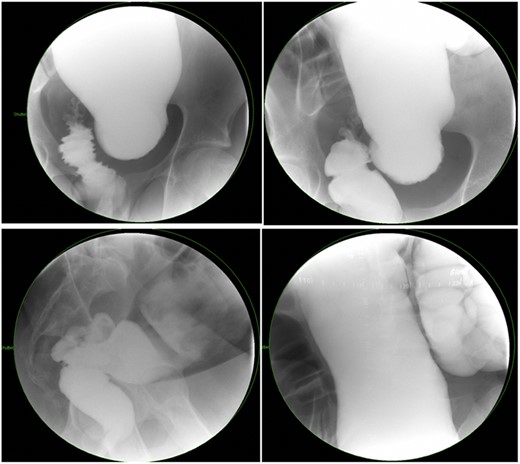

There is a subset of patients in whom primary transanal pull-through in those >2 years of age at the time of surgery is possible. While a previous case series reported that 18.8% of their late-diagnosed HD patients underwent transanal primary pull-through, these authors did not describe outcomes or reasons for choosing the operative approach [7]. In case series, the characteristics of patients who were able to undergo primary transanal-only pull-through include overall earlier age (2–6 years) vs. those diagnosed later. On contrast enema, they exhibited a limited degree of megacolon (Figs 1 and 2). Proximal colonic dilation was absent in all four patients that we felt were good candidates for a transanal-only approach. However, proximal colonic dilation (proximal of the sigmoid) was visualized in 15 patients, and therefore, a transanal-only approach was not offered. The ability to identify a clear transition zone low in the rectosigmoid was also observed in each patient. Finally, the ability to empty the colon preoperatively whether through laxatives or rectal irrigations was also present.

Representative contrast enema study of an older child with a large amount of proximal colonic dilation of the sigmoid and descending colon, seen here across multiple views during contrast enema (Not a candidate for transanal only).

Prior to beginning the pull-through, the colon should be irrigated to make sure that any retained fecal matter has been cleared. Careful assessment of the transition zone and confirmation of minimal proximal colonic dilatation allows for prone-only positioning and a transanal-only approach (Fig. 1). The Lone Star retractor and full-thickness dissection begin 1.0 cm proximal to the dentate line in the Swenson plane. Biopsies should be taken in a single line so as not to lose orientation [8] and 10–15 cm past the positive biopsy for ganglion cells to assure that normal caliber colon is reached before performing the anastomosis. Challenges with the transanal-only approach occur when there is a large amount of proximal colonic dilation, and therefore, in this instance, we recommend a laparoscopic approach for intraoperative mobilization of the descending and proximal colonic mobilization off the left retroperitoneum [9]. If at the time of anastomosis of the dilated ganglionated bowel, anal caliber size discrepancy is encountered a trick can be employed by placing four quadrant sutures and then bisecting each quadrant again and again with interrupted sutures [10].